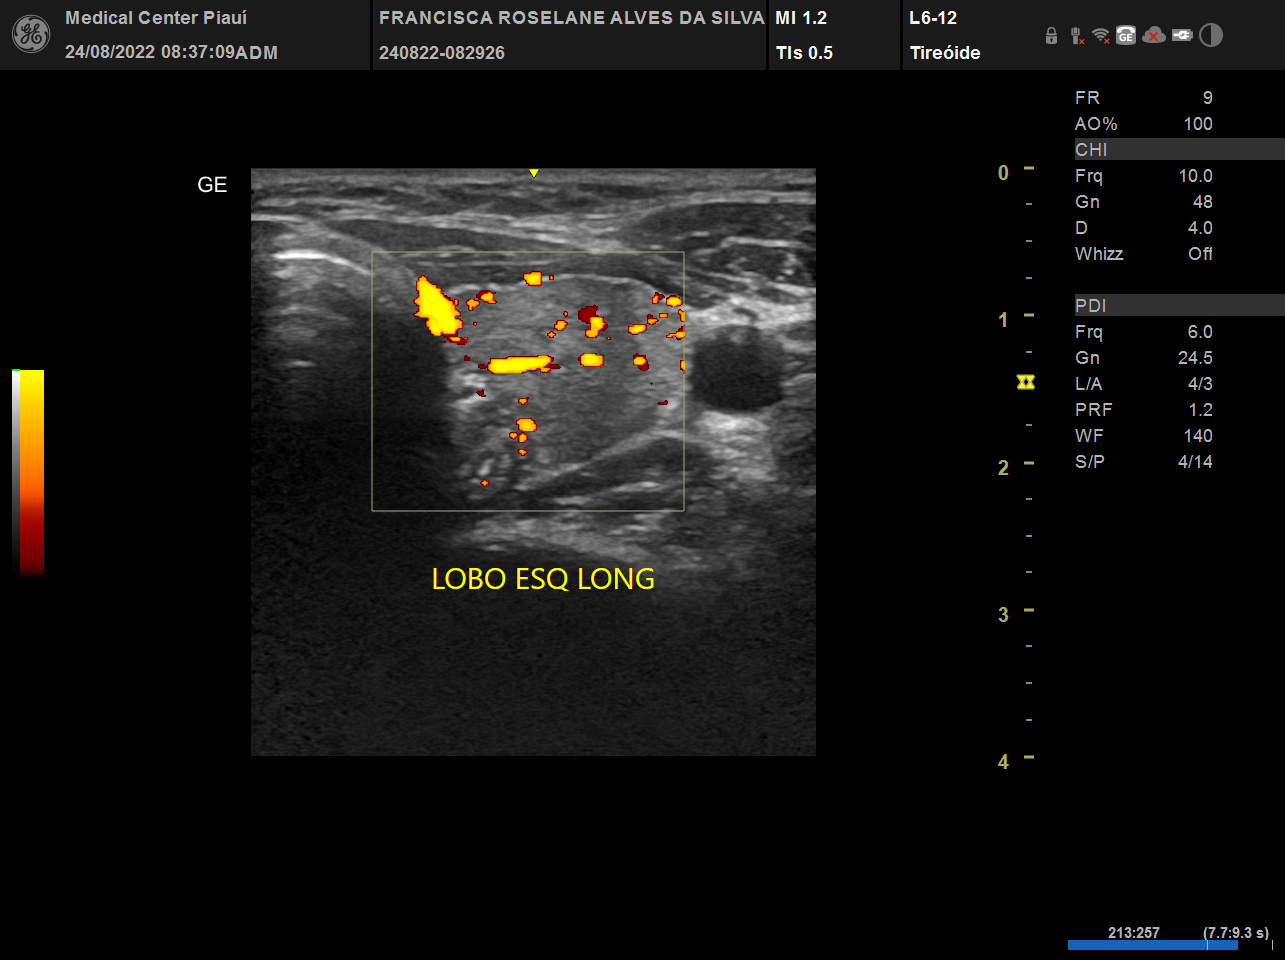

Tireoide

USG, TC e RN de tireoide

Vamos esclarecer as principais dúvidas de como tratar os portadores de hipotireoidismo, hipertireoidismo, nódulo de tireoide, câncer de tireoide. Além disso um treinamento sobre ultrassonografia de tireoide, PAAF e alcoolização percutânea de nódulos (IPE). Ao final, estar apto a decidir quando usar medicações, operar ou usar radioiodoterapia.